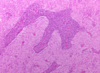

Name the pathologic process.

Name & describe the predominant cell type.

Astrocytosis

Gemistocytic astrocytes: plump, reactive astrocytes with eosinophilic cytoplasm